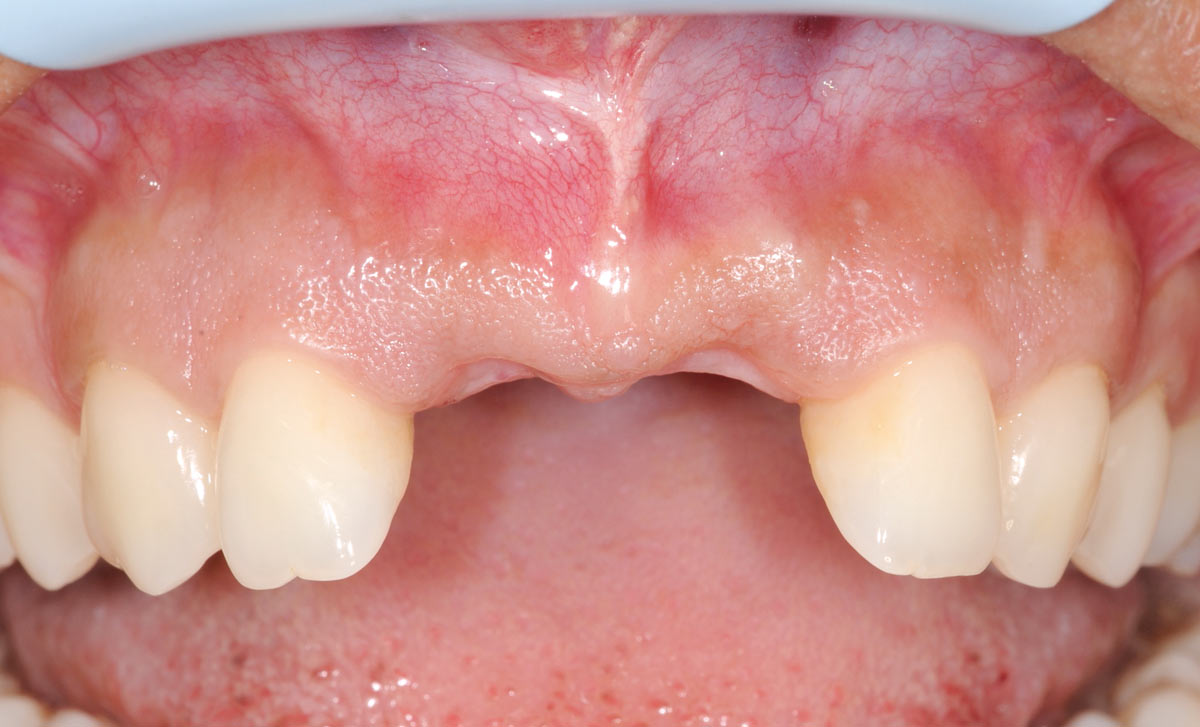

21/26 - 6 months after surgery: healthy soft tissuesBone augmentation in aesthetic zone with maxgraft® bonering - Dr. A. Patel

22/26 - Uncovering the implants 6 months after surgeryBone augmentation in aesthetic zone with maxgraft® bonering - Dr. A. Patel